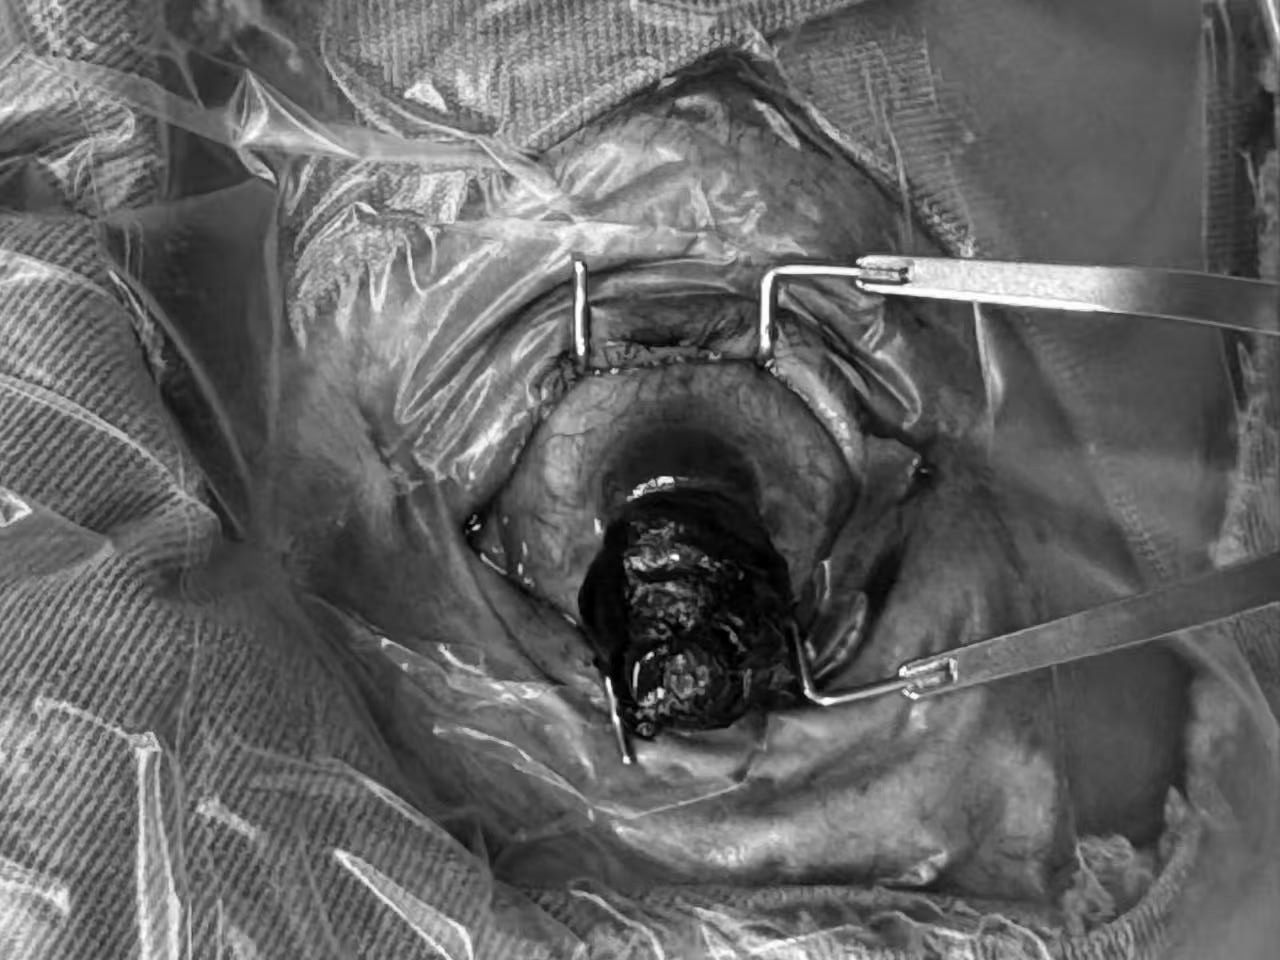

(图二:谢先生左眼暗红色眼内组织脱出如图所示)

入院后,综合眼病科主任王莹及其眼科团队为谢先生展开全面检查,结果显示其左眼混合充血,结膜囊有少许分泌物,全角膜混浊且层次不清,下方存在 6.0mm×4.0mm 大小的穿孔,有 20.0mm×10.0mm×15.0mm 的暗红色眼内物膨出,同时伴随浅前房、房内大量血细胞及凝血块。考虑到眼球完整性已严重破坏,若不及时手术,不仅左眼可能完全丧失功能,还可能威胁右眼健康,王莹主任及其团队迅速制定手术方案,在表面麻醉 + 局部麻醉 + 神经阻滞麻醉下,为其实施 “左眼眼内容物剜出伴巩膜内填充” 手术。王莹主任带领团队凭借丰富经验和精湛技巧,妥善清除脱出组织、处理穿孔部位并进行巩膜内填充,手术顺利完成。术后经局部及全身抗炎、预防感染治疗,谢叔叔眼部疼痛明显缓解,病情逐渐稳定。